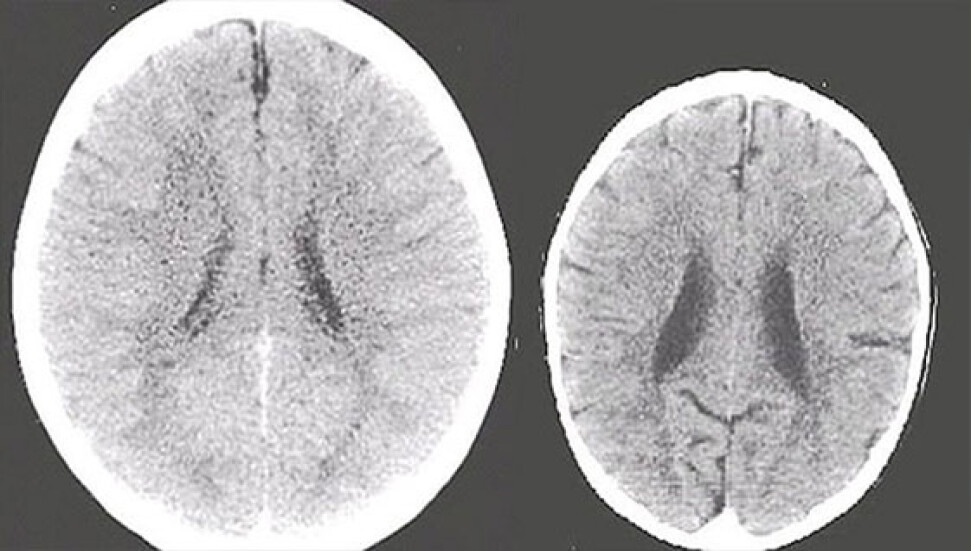

Bunu kanıtlamak için de ailesinin ilgisiyle büyüyen bir çocuk ile ilgisiz büyüyen 3 yaşındaki iki çocuğun beyin hareketlerini ve gelişimini gösteren tomografi sonuçlarını kullandı.

Perry, "Fotoğraflarda da görüldüğü gibi sol taraftaki beyin taraması, ailesinin ilgisiyle yetişen ortalama bir çocuk beyni. Öte yandan sağ tarafta ailesiyle zaman geçirmeyen ve ailesinin ilgisini görmeyen bir çocuğun beyninin taraması var. Bu çocuğun şiddet görmüş olabileceğini de tahmin ediyoruz. Bu taramalar sonucunda, sağ taraftaki çocuğun beyni yaşıtına göre daha küçük" dedi.

Perry, "Sağ taraftaki çocuğun beyninin yeteri kadar gelişmemesi gelecekte hastalıkların da habercisi. Bu durum genelde Alzheimer hastası olan yaşlı bireyylerde görülür. Bu çocuğun hafıza sorunu yaşaması çok olası. Öte yandan bu çocuğun bağlanma sorunları ve sosyal olarak izole bir hayat sürmesi oldukça mümkün" şeklinde konuşarak ailelere uyarıda bulundu.